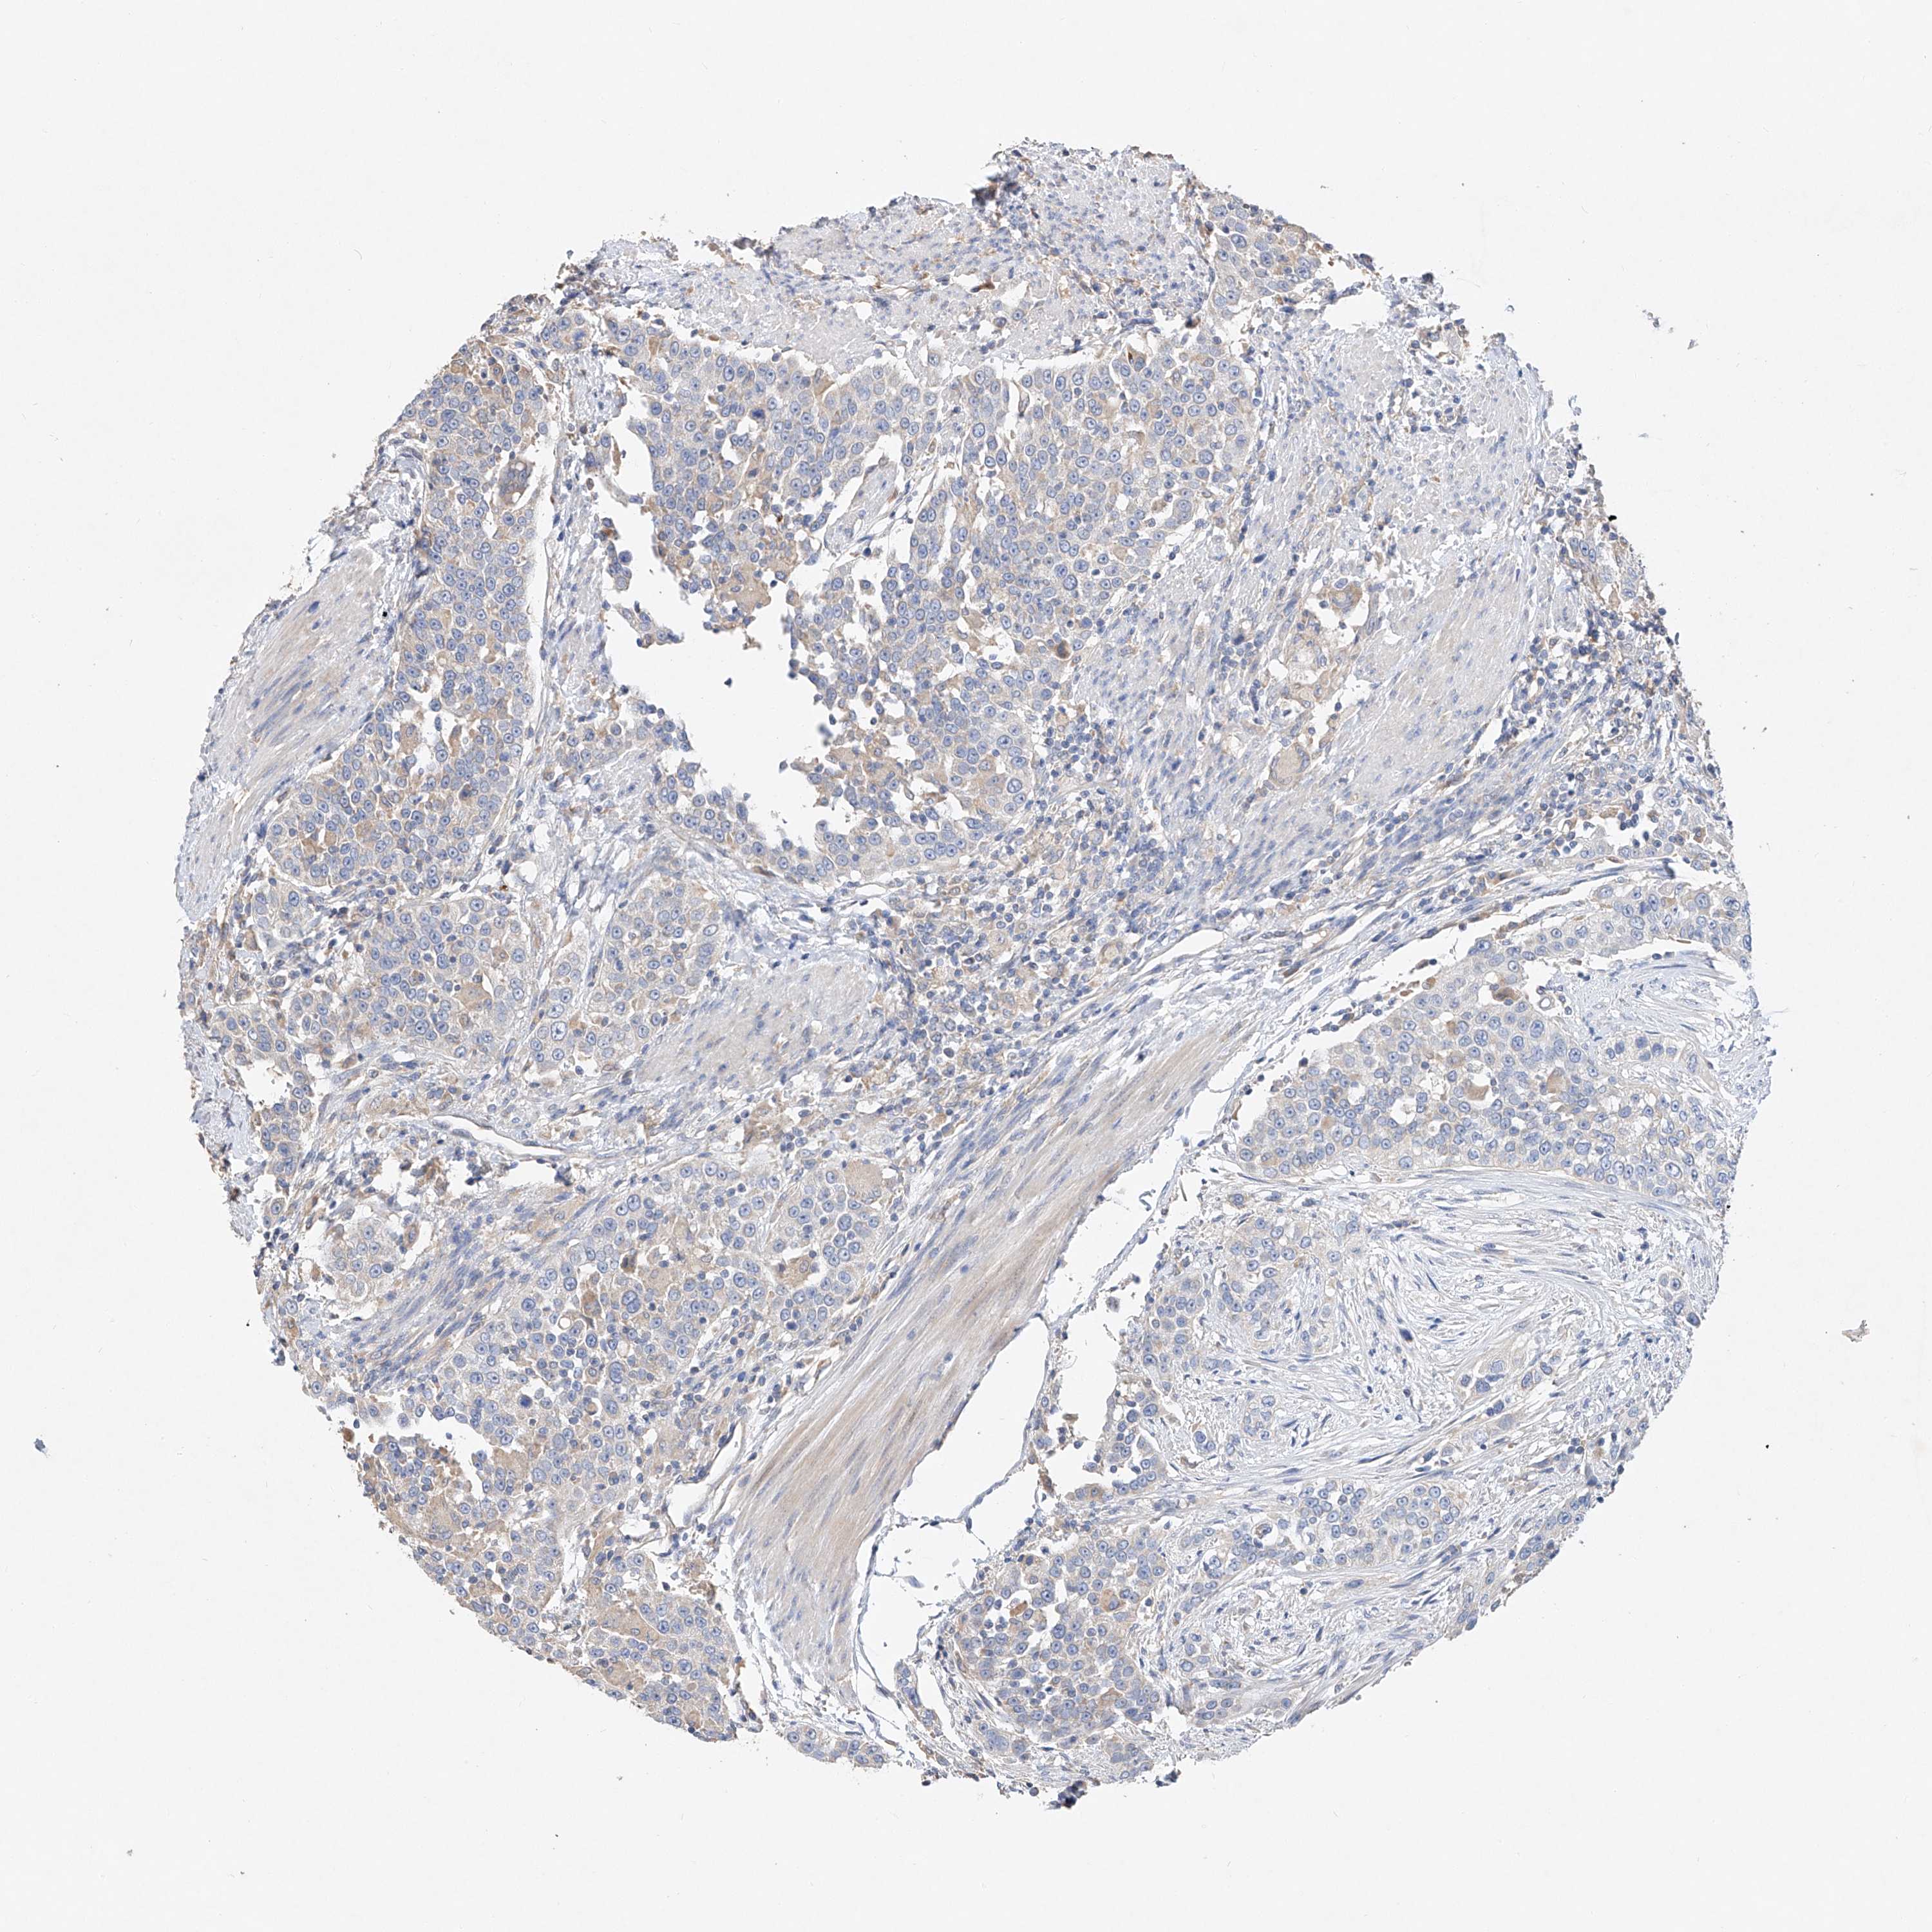

UROTHELIAL CANCER - Protein expressioni

A mouse-over function shows sample information and annotation data. Click on an image to view it in a full screen mode. Samples can be filtered based on level of antibody staining by selecting one or several of the following categories: high, medium, low and not detected. The assay and annotation is described here.

Note that samples used for immunohistochemistry by the Human Protein Atlas do not correspond to samples in the TCGA dataset.

Antibody stainingi

Antibody staining in the annotated cell types in the current human tissue is reported as not detected, low, medium, or high, based on conventional immunohistochemistry profiling in selected tissues. This score is based on the combination of the staining intensity and fraction of stained cells.

Each image is clickable and will lead to virtual microscopy that enables deeper exploration of all samples and also displays staining intensity scores, fraction scores and subcellular localization as well as patient and tissue information for each sample.

Antibody HPA029281

Antibody HPA029282

Urothelial carcinoma, Low grade

Urothelial carcinoma, High grade